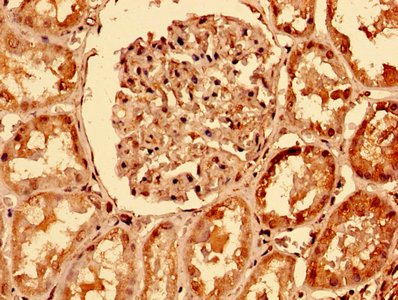

IHC image of CSB-PA023964LA01HU diluted at 1:400 and staining in paraffin-embedded human kidney tissue performed on a Leica BondTM system. After dewaxing and hydration, antigen retrieval was mediated by high pressure in a citrate buffer (pH 6.0). Section was blocked with 10% normal goat serum 30min at RT. Then primary antibody (1% BSA) was incubated at 4°C overnight. The primary is detected by a biotinylated secondary antibody and visualized using an HRP conjugated SP system.